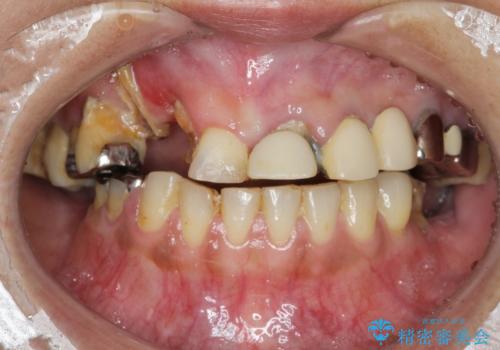

痛くて噛めない インプラントで全て治療したい

- 痛くて噛めない、これまでだましだまし治療をしてきたがこれを機にすべてきっちりと治したい、口の中の悩みを解決したいと来院されました。

抜歯や歯周病治療、欠損補綴を含め、全顎的な治療を計画・提案します。